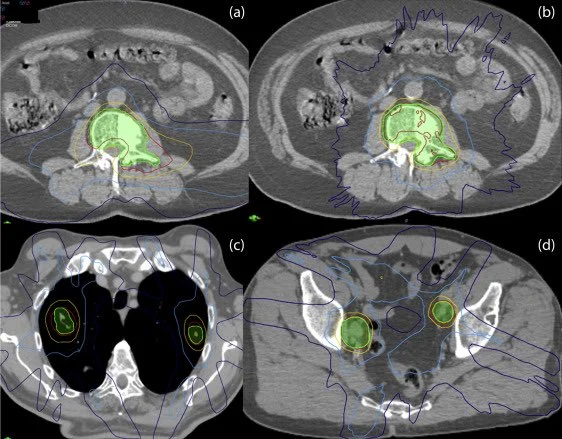

Title: Top 10 Tips for Stereotactic Body Radiation Therapy Contouring and Planning in Oligometastatic Disease: Lessons Learned From the UK SBRT QA Program

Authors: Patricia Díez, Emma M. Dunne, Rushil Patel, Christopher Dean, Sarah Osman, Fiona McDonald